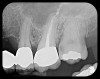

Fig 4. Severe dilaceration of root of tooth No. 17 and

curvature of roots of No. 18. Mandibular canal and inferior border of mandible are

easily visualized. If extraction of No. 17 is planned, a 3D CBCT study is required

due to proximity of tooth root to vascular and inferior alveolar nerve contents of

mandibular canal and possibility of surgical complications.

Figure 4

Fig 5. Bilateral concerns for this patient are evident on these PSP

radiographs. Tooth No. 17 may exhibit pathology distal to the root. In

addition, extreme length of root of tooth No. 32 through the entire height

of the body of the mandible is cause for concern if extractions of Nos.

17 and 32 are planned. Three-dimensional CBCT study and alerts to

the patient as to the potential surgical complications on extractions are

required in this instance. There is no benefit to panoramic radiography

in this case.

Figure 5

Fig 6. PA radiograph showing 90-degree dilacerations of

mesial and distal roots of tooth No. 32 and intersection of mandibular

canal with these roots. Extraction of tooth No. 32 requires 3D study, and

patient was advised as to this necessity.